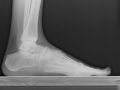

xrayThe U.S. Food and Drug Administration has approved the Scandinavian Total Ankle Replacement (S.T.A.R.) System for patients with arthritic or deformed ankles. The S.T.A.R. Ankle, developed by Small Bone Innovations of Pennsylvania, relies on bearings that move across a surface of flexible plastic. The device was designed as an alternative to traditional fusion surgery, in which the shin bone is cemented to the talus bone in the ankle. Fusion surgery typically stabilizes the ankle, but reduces the foot’s range of motion. The S.T.A.R. device may allow for greater rotation and movement in the ankle. It is the first and only FDA-approved device of its kind.